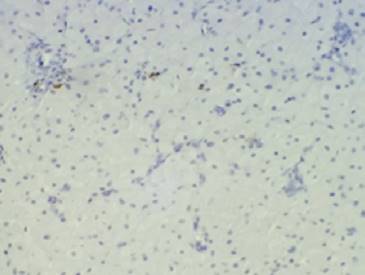

El estudio anatomopatológico muestra una proliferación difusa de células de gran talla con citoplasma amplio y granular, con núcleos pequeños, algunos lateralizados. Se encuentra revestida por una delgada capa mucosa pavimentosa que muestra focos de ulceración. Presenta rica red vascular estromal. Se solicita técnica de PAS (ácido peryódico de Shiff) que es positiva en el citoplasma de las células granulares (Figura 3). La inmunomarcación con la proteína S100 es negativa en las células de la proliferación (Figura 4). Estos hallazgos son consistentes con el diagnóstico de tumor de células granulares congénito (épulis congénito).

Figura 4: 100x. Las células tumorales no muestran inmunomarcación con el anticuerpo antiproteína S100.